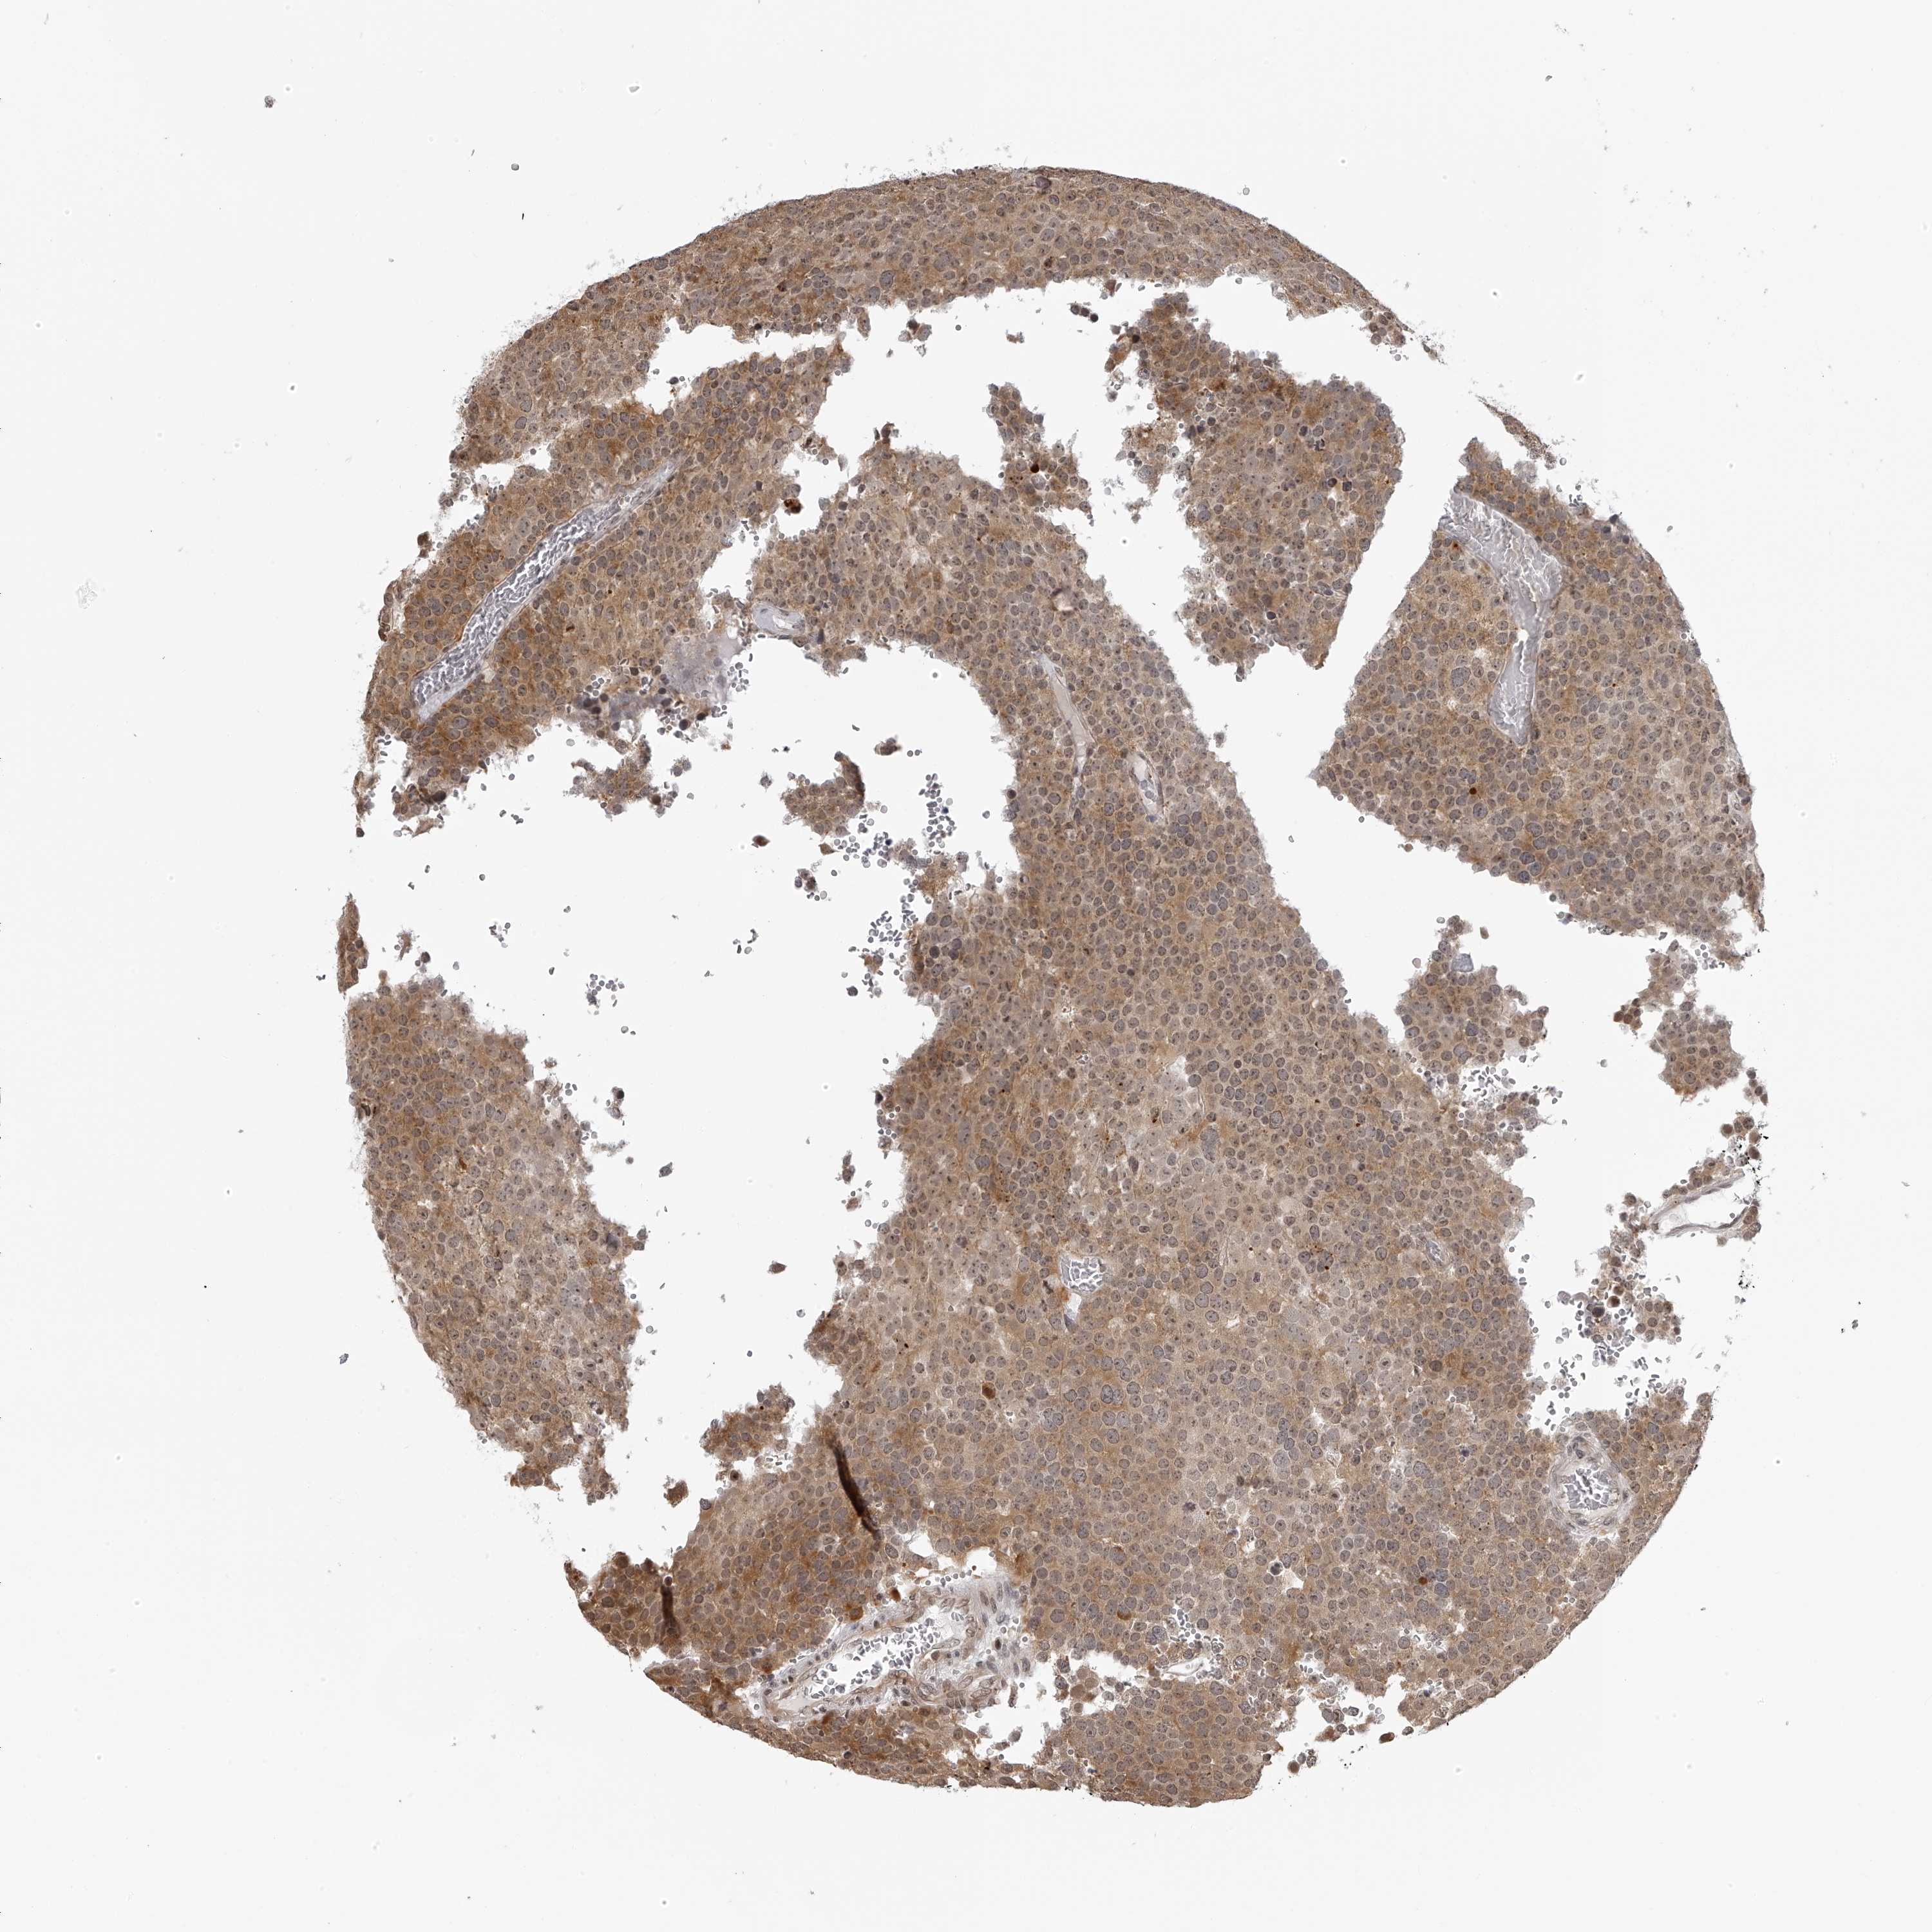

TESTIS CANCER - Protein expressioni

A mouse-over function shows sample information and annotation data. Click on an image to view it in a full screen mode. Samples can be filtered based on level of antibody staining by selecting one or several of the following categories: high, medium, low and not detected. The assay and annotation is described here.

Note that samples used for immunohistochemistry by the Human Protein Atlas do not correspond to samples in the TCGA dataset.

Antibody stainingi

Antibody staining in the annotated cell types in the current human tissue is reported as not detected, low, medium, or high, based on conventional immunohistochemistry profiling in selected tissues. This score is based on the combination of the staining intensity and fraction of stained cells.

Each image is clickable and will lead to virtual microscopy that enables deeper exploration of all samples and also displays staining intensity scores, fraction scores and subcellular localization as well as patient and tissue information for each sample.

Antibody HPA028020

Antibody HPA028095

Antibody HPA028333

Staining

High

Medium

Low

Not detected

Intensity

Strong

Moderate

Weak

Negative

Quantity

>75%

75%-25%

<25%

None

Location

Nuclear

Cytoplasmic/membranous

Cytoplasmic/membranous,nuclear

Carcinoma, Embryonal, NOS

Seminoma, NOS